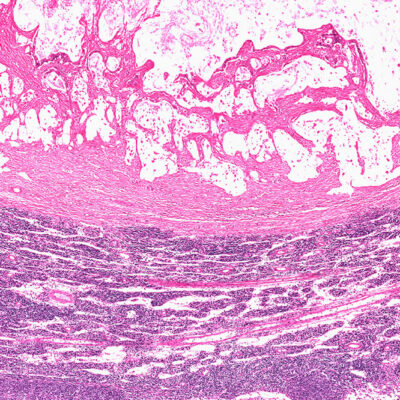

A gastrointestinal stromal tumor begins in the glandular cells present in the body’s digestive system. An accurate diagnosis is essential to ensure the right treatment is provided for this condition. There are several side effects to the treatment, such as nausea, vomiting, and bowel obstruction. All these issues make it harder for a person to consume the required amount of food in the day.